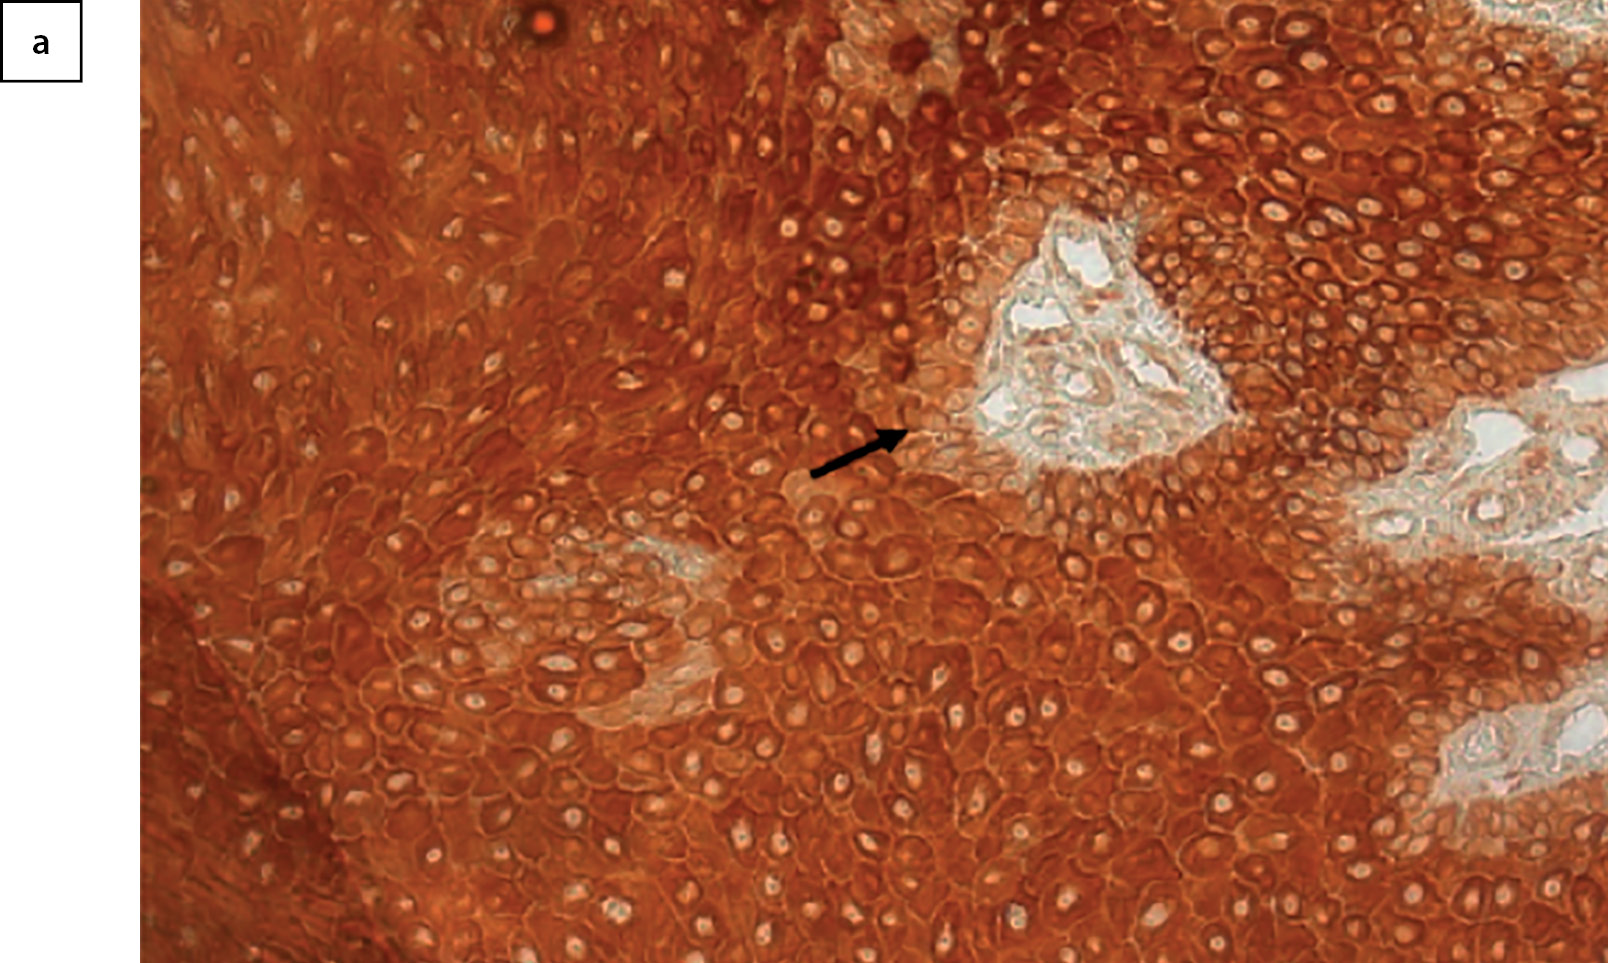

Все слои эпидермиса экспрессировали маркер пролиферативной активности Ki-67 (рис. 3), более интенсивное окрашивание отмечалось в базальном слое. Интенсивность пролиферации эпидермиса в течение периода наблюдения значимо не менялась (рис. 4, p=0,447 для фактора срока от начала терапии).

Рисунок 3. Иммуногистохимическое окрашивание на Ki-67 участка кожи,

обращенного в сторону края раны. 24-е сутки от начала терапии.

Коричневое окрашивание — наличие маркера (стрелка).

Базальный слой эпидермиса окрашен сильнее (стрелка). Х200.

Все слои эпидермиса экспрессировали рецепторы к медиатору парасимпатической нервной системы — ацетилхолину — α7nAChR (рис. 5а). По сравнению со стартом терапии к 10-му и 24-му дням отмечалось увеличение плотности экспрессии маркера. По результатам дисперсионного анализа, влияние фактора времени после начала терапии оказывается значимым (рис. 5б, p=0,031). По результатам апостериорных сравнений методом наименьшей значимой разницы, наблюдаемое влияние фактора времени связано с большей плотностью холинорецепторов в эпидермисе на 24-е сутки после начала терапии, относительно 0 точки (p=0,023). Точка 10 дней после начала терапии от остальных временных точек не имела значимых различий. В целом, количество рецепторов в течение наблюдения в коже увеличивалось к 24-му дню.

Рисунок 5а. Иммуногистохимическое окрашивание на α7nAChR участка кожи,

обращенного в сторону края раны. Коричневое окрашивание — наличие маркера.

В отличие от окрашивания на Ki-67, окрашивание базального слоя (стрелка) слабее,

чем у остального эпидермиса. Х200.